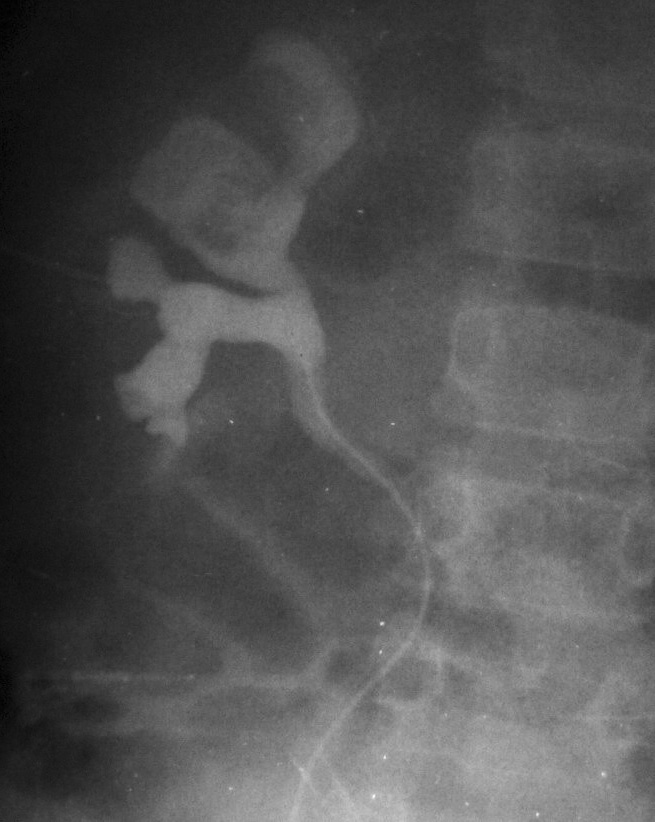

De los pacientes diagnosticados de carcinoma de células renales (n= 4) (con edad y presentación mostrados en la tabla 2) en dos casos se localizaron masas renales en la corteza renal, con infiltración del sistema pielocalicial. De estos dos, uno demostró fuga de contraste del sistema excretor en la radiografía abdominal post-TC con contraste, y el otro invasión de médula con extensión hasta el uréter proximal (fig. 5). En un único caso se apreciaron abundantes calcificaciones grumosas intratumorales dispersas (fig. 6).

Fig. 5. Carcinoma de células renales. (A) Tomografía computarizada abdominal con contraste intravenoso. Corte axial sobre hilios renales. Riñón derecho aumentado de tamaño con discreto retraso de su función. Masa hipodensa central con extensión al sistema colector y escasa captación de contraste. (B) Pielografía ascendente del riñón derecho. En cálices del polo renal superior existe un defecto de repleción junto a dilatación y deformidad por tumoración que ocupa el sistema colector.